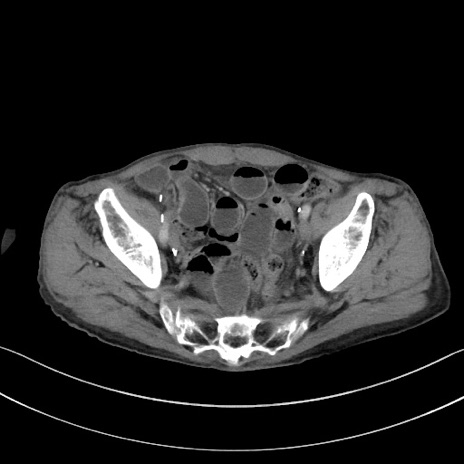

【症例】 70歳代男性

【主訴】右鼠径部腫瘤、疼痛

【現病歴】本日朝より上記主訴あり、受診。

【既往歴】膀胱癌にて膀胱全摘、両側尿管皮膚瘻

【データ】WBC 5600、CRP 0.56